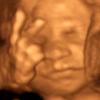

‘V’ 그리는 27주 태아의 초음파 사진 화제

2009-11-10 나우뉴스 -